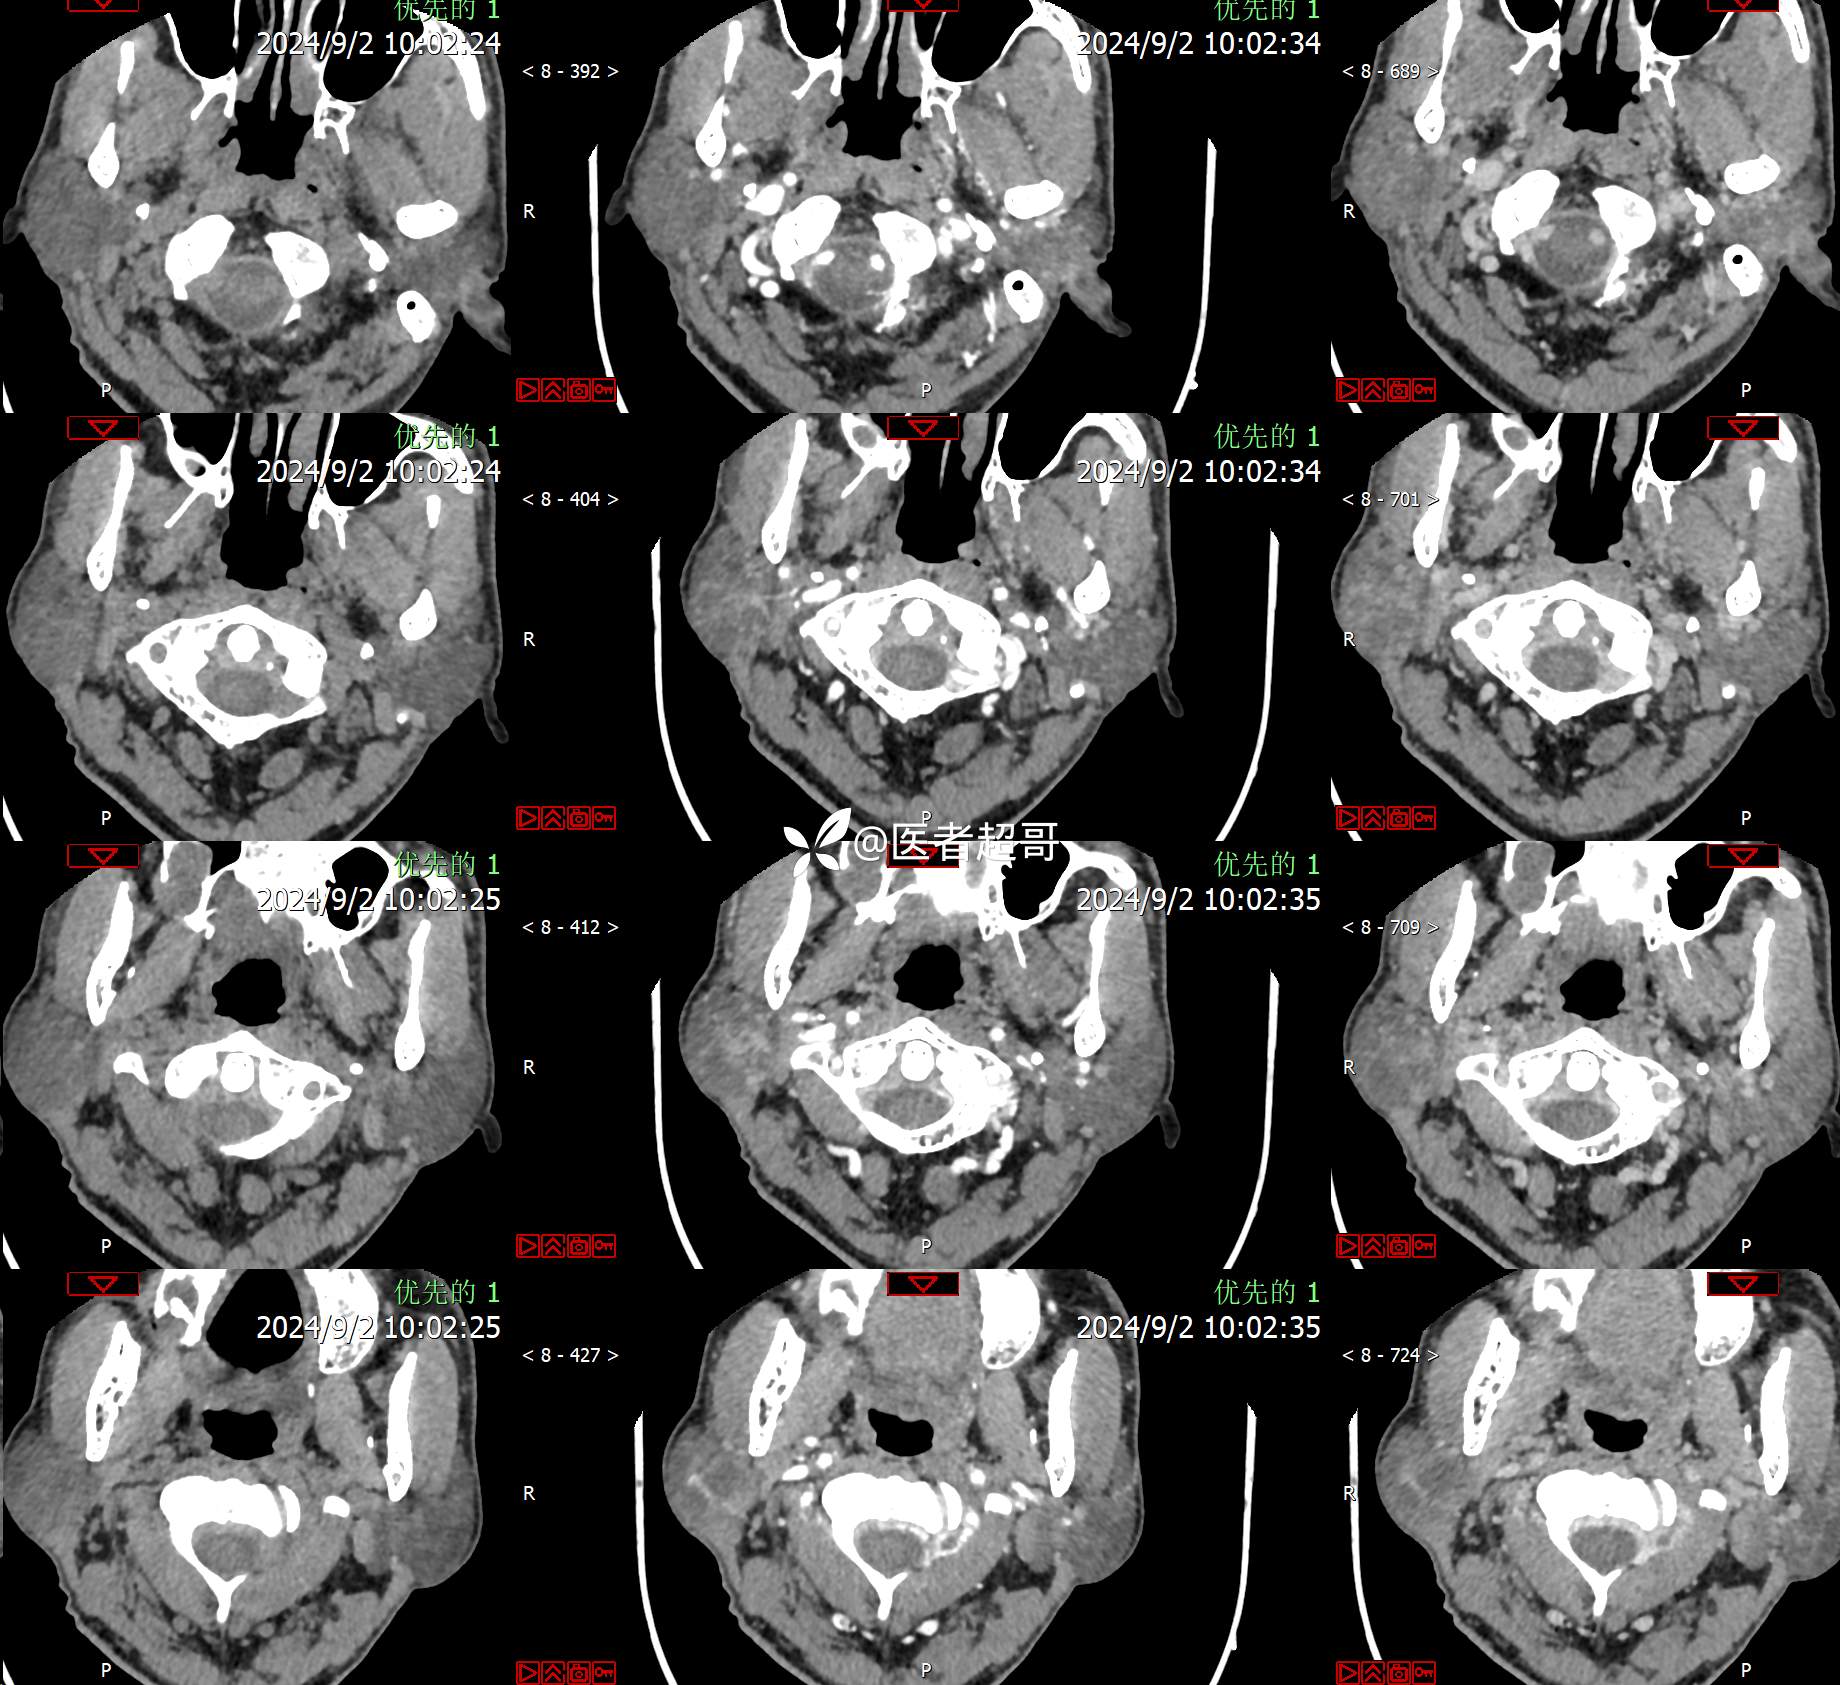

腮腺肿物,CT、MRI齐全,情诊断分析,有详细术程及病理!

主诉:发现右腮腺肿物6个月。

现病史:患者于6个月前无明显诱因发现右侧腮腺区肿物,无疼痛,无局部皮肤破溃,无吞咽困难,无听力下降,无发热,无头痛头晕,患者自发病后在外未治疗,6天前于当地卫生院检查建议手术,为求手术治疗,来我院就诊,门诊以“腮腺肿瘤(右)”收入我院。患者自发病以来,神志清楚,精神可,饮食可,睡眠可,大便正常,小便正常,体重无明显变化。